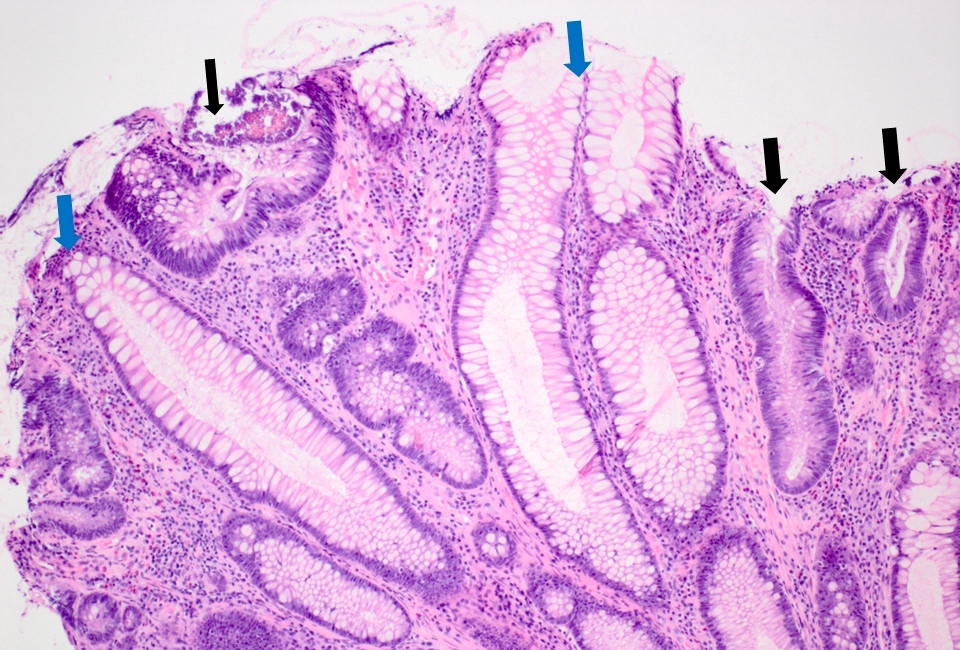

Microscopic (histologic) description

- Low grade dysplasia:

- Preserved nuclear polarity

- Pseudostratified, crowded, elongated and hyperchromatic nuclei

- Lack of surface maturation, i.e. abnormalities persist to surface

- Indefinite for dysplasia:

- Reserved for cases when distinction between dysplasia and reactive epithelial atypia cannot be made

- Mucosal erosion or ulceration (precluding assessment of surface maturation) or prominent inflammation may be sources of difficulty

Microscopic (histologic) images